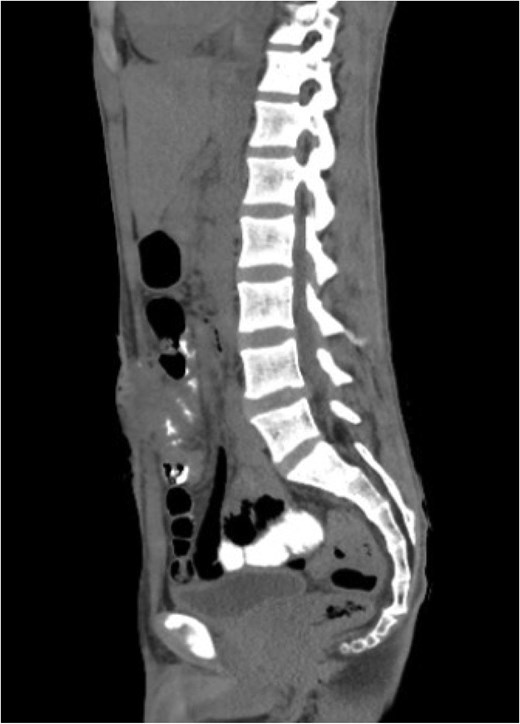

Abdominal computed tomography (CT) revealed a dilated appendix filled with fluid, measuring 2.7 × 8 cm on the short and long axes, respectively, with significant surrounding fat stranding, free fluid, and reactive inflammatory changes involving the terminal ileum and cecum, along with a few prominently enlarged regional lymph nodes (Fig. 1). Other investigations revealed a hemoglobin level of 12.6 g/dL, white blood cell count of 11.3 × 109/L with an absolute neutrophil count of 10.3 × 109/L, and erythrocyte sedimentation rate of 64 mm/h.

Axial view of abdominal and pelvic CT scan with oral and IV contrast shows enlarged appendix, measured 2.7 in diameter. Surrounded by fat-stranding, free fluid, with enlarged reactive lymph nodes (arrow).